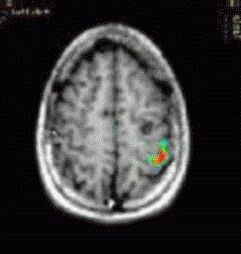

Case 3

Patient Male patient, age 14, with seizures

Paradigm Tapping task

ON: Alternating Finger Tapping with the right hand

OFF: Think of nothing

Results Cortex of the left central sulcus was strongly activated. The relation to the tumor is clearly depicted by the images.

Comments The tumor was resected without postoperatory motor deficit